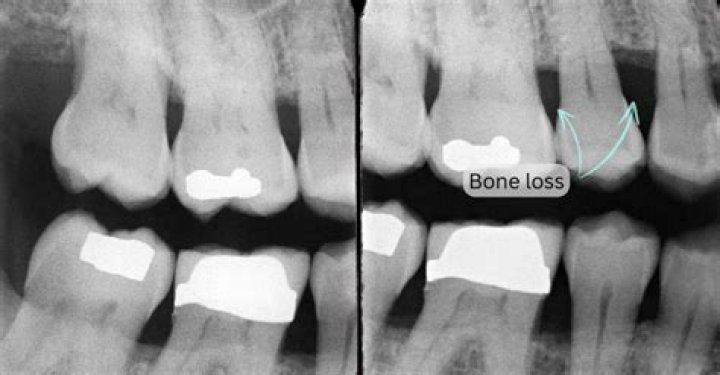

Can you see bone loss on an X-ray?

However, x-rays are note used to diagnose osteoporosis. X-rays can only detect bone loss after 25-40 percent of the skeleton has been depleted and should not be used to identify the presence of osteoporosis.

An X-ray may be helpful in the diagnosis of osteoporosis. The main X-ray finding suggestive of osteoporosis is the bone mass loss. Primarily, the loss is mainly in bony trabecula, than the cortex. The most common bones monitored for osteoporosis are the femoral neck, lumbar vertebrae, and calcaneus.